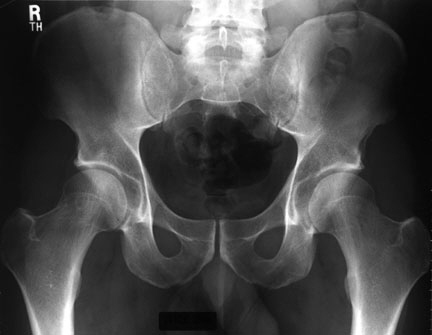

En ce qui concerne l’ostéochondrite de hanche, la radiographie de face et de profil permet de reconnaître la lésion (signes discrets au début puis signes de gravité: excentration et aplatissement de la tête du fémur...), d'en préciser l'étendue et d'apprécier les stades évolutifs (successivement): phase de nécrose du noyau épiphysaire; phase de résorption (fragmentation); phase de reconstruction; phase de remodelage.

Images radiologiques

Illustration 4 : Évolution radiologique de l'ostéochondrite (d'après [3])

Illustration 5 : Signes radiologiques initiaux de l'ostéochondrite (d'après [3])

Retour sommaire

Illustration 6 : Stade très avancée : fragmentation de l'épiphyse droite (d'après [3]).

Illustration 7 : Coxa plana à droite.

Illustration 6 : Stade très avancée : fragmentation de l'épiphyse droite (d'après [3])

Illustration 7 : Coxa plana à droite